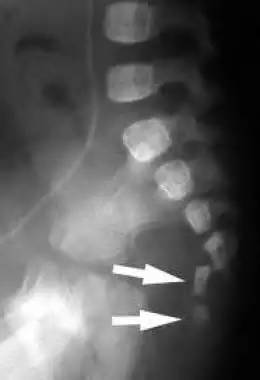

很多人不知道尾椎是啥。就是如图所示的那个小骨头。

尾椎骨折的症状主要是疼痛,包括坐着痛,排便痛,骨头的按压痛等。诊断主要是通过典型的病史和疼痛的症状,以及相关体检,必要时需要做拍片子看一下受伤的程度,排除是否有除了尾椎之外的骨折。